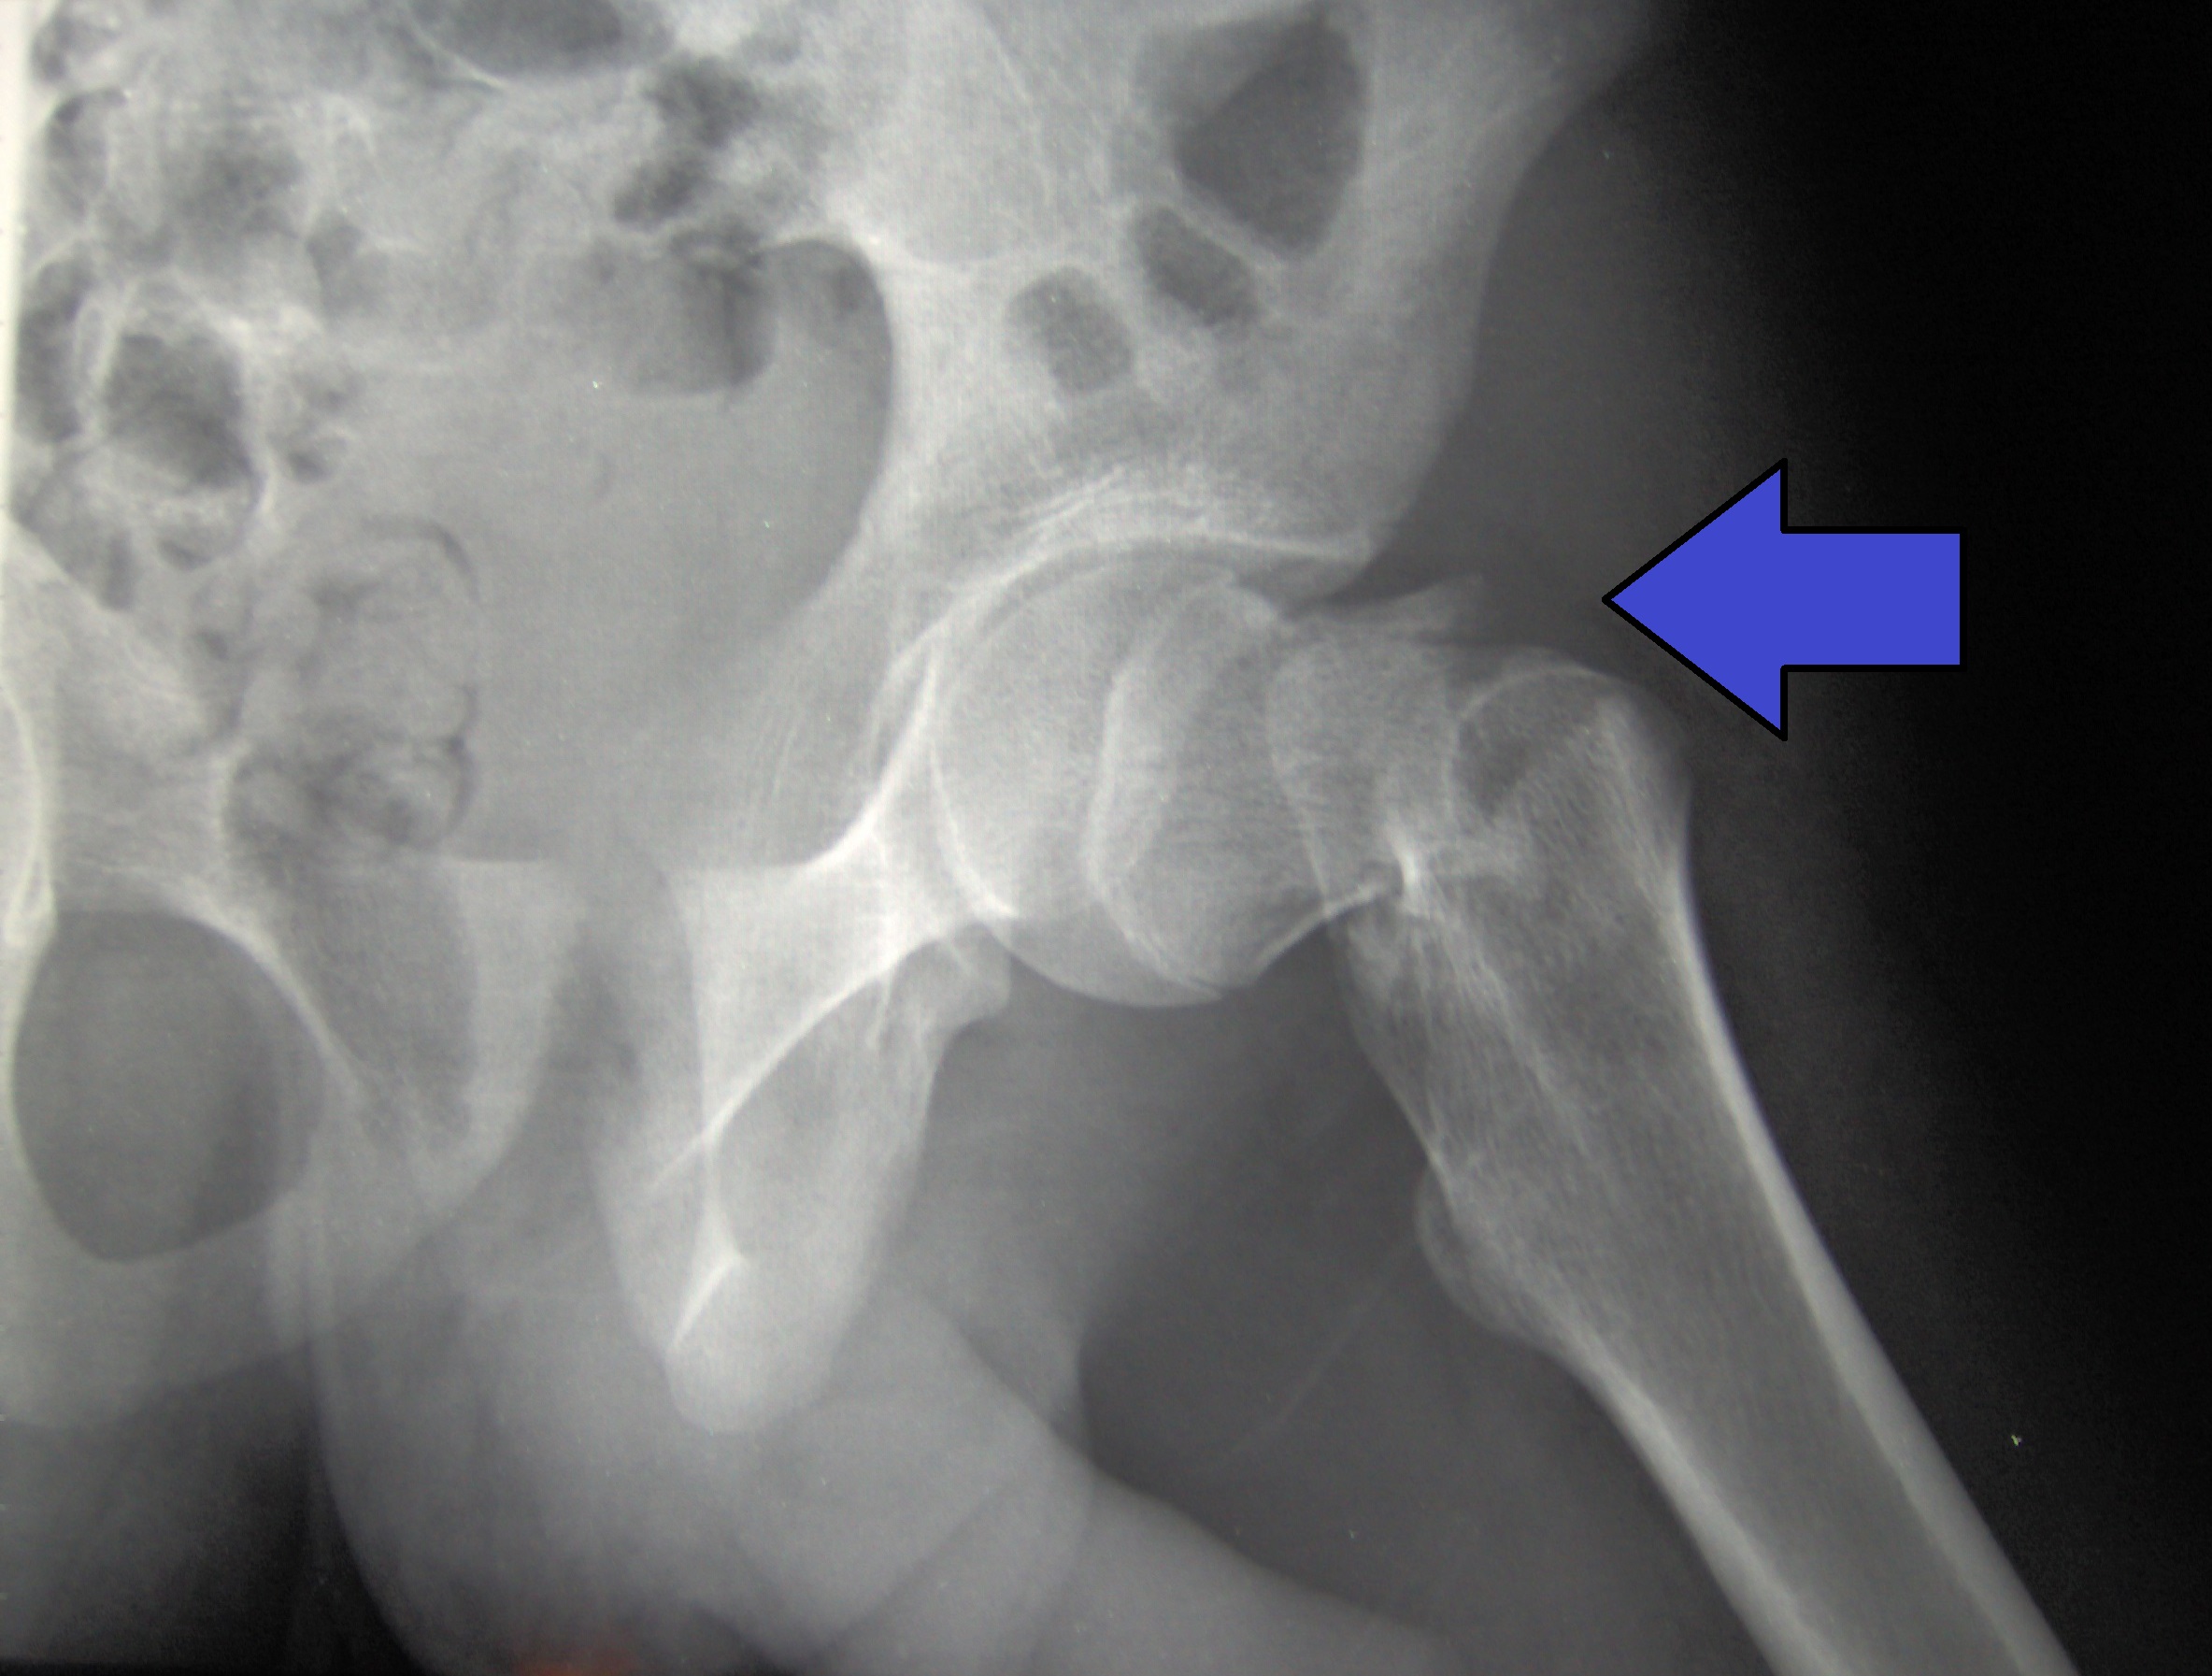

Dolor luego de la anestesia general o espinal para la cirugía de fractura de cadera

14 junio 2022

El dolor intenso es común después de una fractura de cadera. La anestesia espinal se asoció con más dolor en las primeras 24 horas después de la cirugía y más uso de analgésicos recetados a los 60 días en comparación con la anestesia general. Annals of Internal Medicine, 14 de junio de 2022.